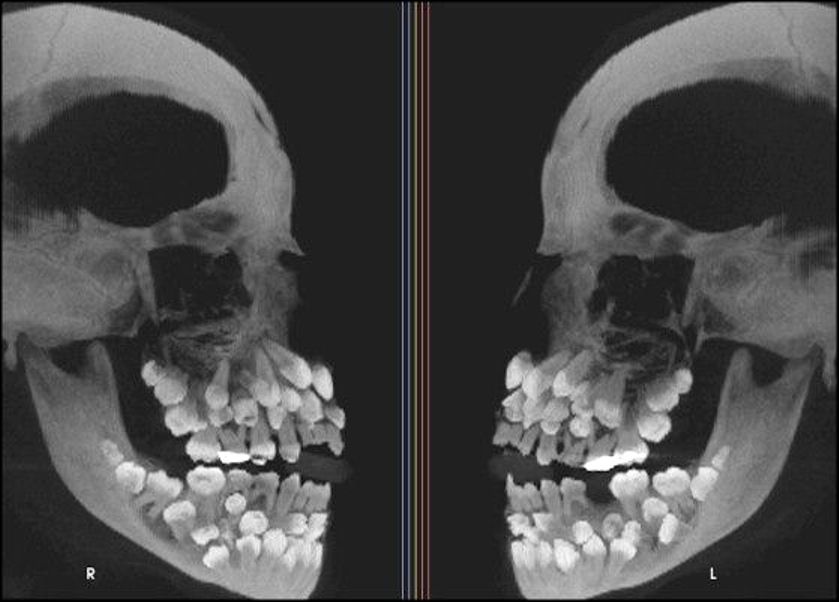

EXTREME CASES

BELOW ARE X-RAYS OF ACTUAL PATIENTS

Hyperdontia is the condition of having supernumerary teeth, or teeth that appear in addition to the regular number of teeth. They can appear in any area of the dental arch and can affect any dental organ.

There is evidence of hereditary factors along with some evidence of environmental factors leading to this condition. While a single excess tooth is relatively common, multiple hyperdontia is rare in people with no other associated diseases or syndromes. Many supernumerary teeth never erupt, but they may delay eruption of nearby teeth or cause other dental or orthodontic problems. Molar-type extra teeth are the rarest form. Dental x-rays are often used to diagnose hyperdontia.

It is suggested that supernumerary teeth develop from a third tooth bud arising from the dental lamina near the regular tooth bud or possibly from splitting the regular tooth bud itself. Supernumerary teeth in deciduous (baby) teeth are less common than in permanent teeth.